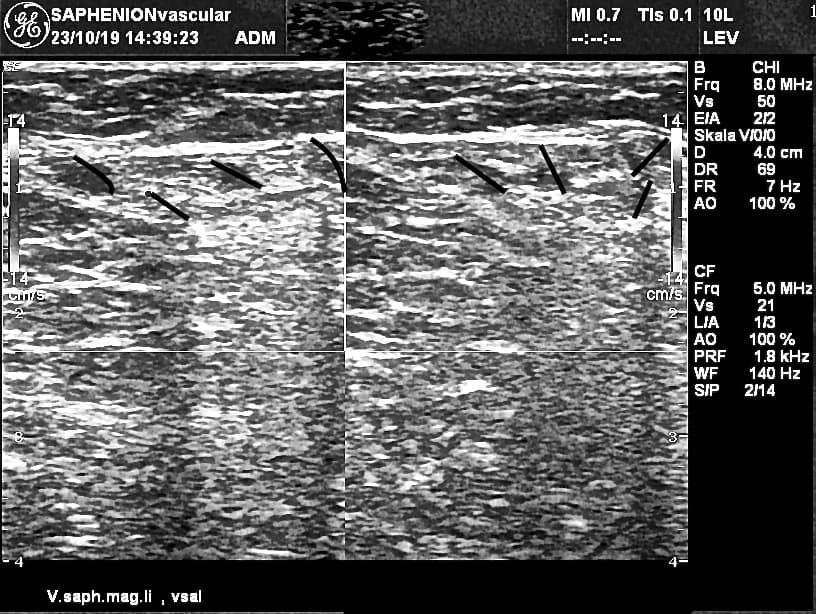

VenaSeal of junction of GSV and SSV – ultrasound control

Utzius: Ultrasound pictures